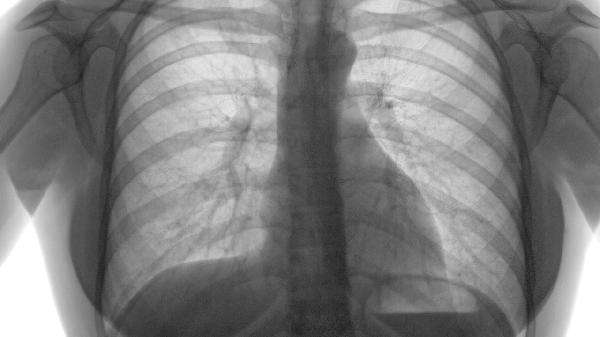

肺气肿和肺结节多数情况下不会直接癌变,但存在一定风险。肺气肿属于慢性阻塞性肺病,癌变概率较低;肺结节癌变风险与结节性质相关,主要影响因素有结节大小、生长速度、边缘特征、钙化程度及患者吸烟史等。

肺气肿是肺泡壁破坏导致的气腔永久性扩张,属于慢性炎症性病变。其癌变风险主要与长期烟草暴露相关,长期吸烟者可能合并肺癌,但肺气肿本身并非癌前病变。临床需警惕持续咳嗽、痰中带血等预警症状,建议定期进行低剂量CT筛查。

肺结节分为实性、磨玻璃和部分实性三类,其中部分实性结节恶性概率最高约7%-10%。直径小于6毫米的结节恶性率低于1%,而大于8毫米的结节需结合PET-CT或穿刺活检进一步评估。随访观察中结节体积倍增时间小于400天需高度警惕。

吸烟指数超过20包年、有恶性肿瘤家族史、接触石棉或氡气等职业暴露人群风险显著增高。结节边缘毛刺征、分叶征、胸膜牵拉等影像学特征提示恶性可能,需结合肿瘤标志物如CEA、CYFRA21-1辅助诊断。